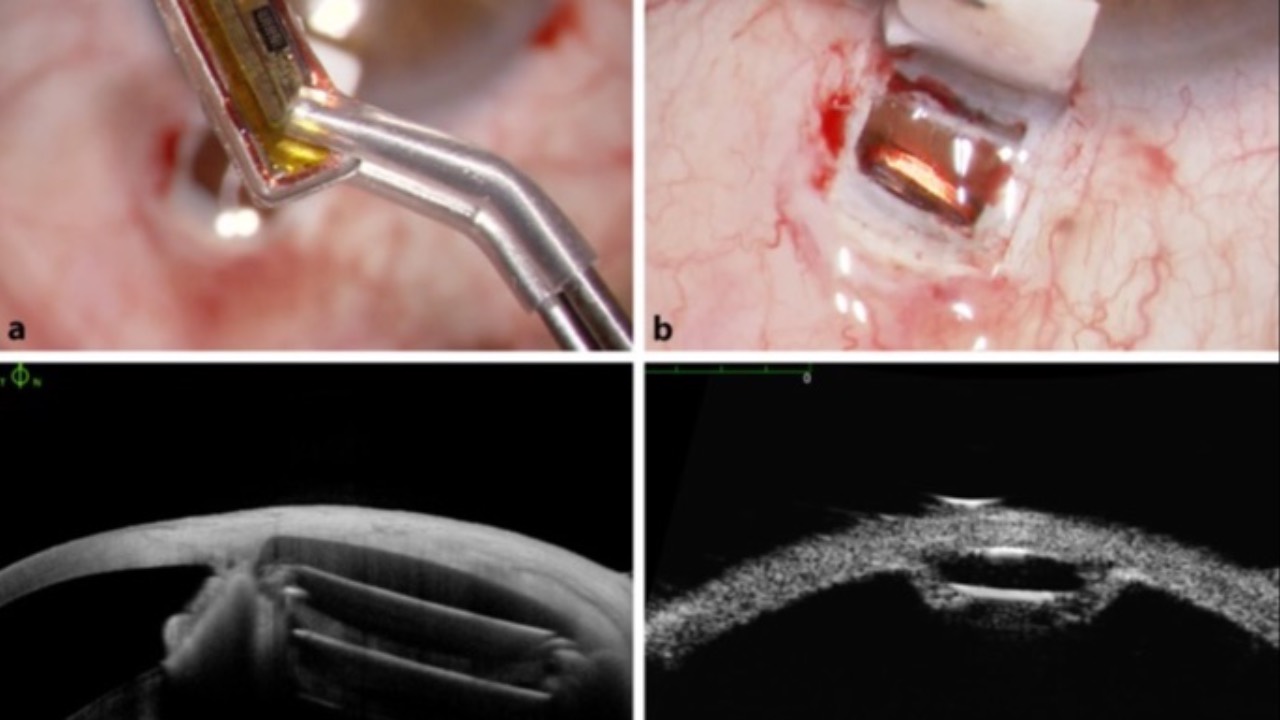

LABS & IMAGING FOR PRIMARY EYE CARE

BOOK & COURSE BUNDLE

Are you an optometrist hesitant to order and utilize laboratory diagnostics or imaging for your patients? Are you a student uncomfortable or unsure where to start?

Check out the Book & Course Bundle: